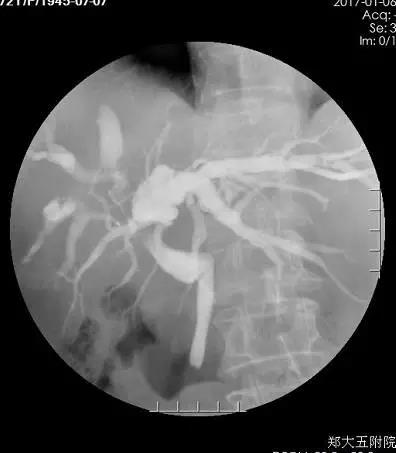

术后2周胆道造影

术后15天,樊奶奶做了经PTCD管给胆管造影,结果发现肝内外胆管已经通了。术后40天,樊奶奶又来院复查,她告诉李晓勇教授自己的食欲现在非常好,生活质量比以前明显提高。陈艳军副主任为樊奶奶复查了肿瘤标记物,结果发现肿瘤标志物已经完全恢复正常。